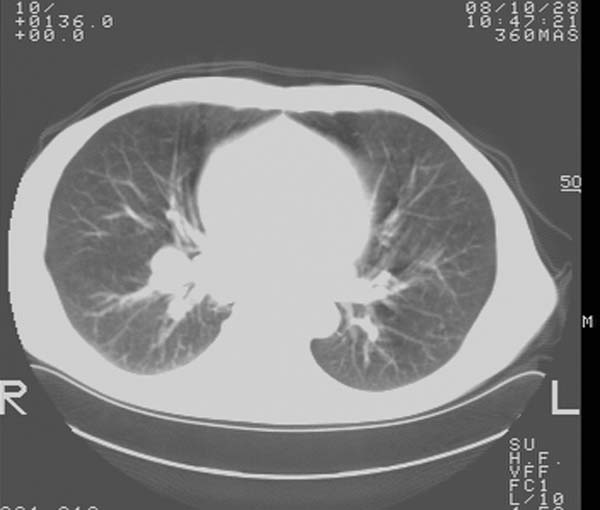

m,65y。半年前发现颈小结节,逐渐增多增大,现双侧耳后、颌下及颈部表浅淋巴肿大。胸片示双肺门增大。外院曾穿刺诊断为淋巴结核。在我科作胸腹部ct,我们觉得外院病检有误。现将图像上传请战友讨论。

纵隔内及腹膜后广泛淋巴结肿大,脾大,肝内似可见低密度影,结合病史半年前发现颈小结节,逐渐增多增大,现双侧耳后、颌下及颈部表浅淋巴肿大。考虑淋巴瘤。

纵隔,双肺门腹膜后多发淋巴结重大,非融合,肝脾轻度肿大,双肺野弥漫性小结节;考虑淋巴瘤,结节病可能性

纵隔内,双肺门、腋窝及腹膜后多发肿大淋巴结影,肺内小结节影,肝脾体积增大,支持淋巴瘤。肝内多发低密度影,考虑小囊肿。